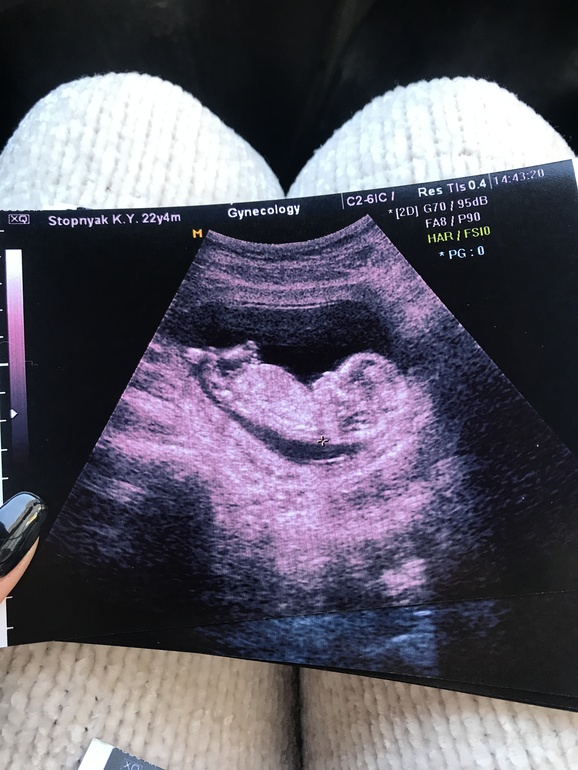

На этом фото видно половой бугорок?

УЗИ, КТГ, доплерМожет по бугорку можно будет сделать предположение кто же там?) или не видно?)

Мне с таким же бугорком узист сказала точно мальчик, посмотрим что ещё скажут на втором скрининге. Можете посмотреть фото с УЗИ у меня в дневнике. С дочкой был другой бугорок:)

Точно похоже на мальчика, у моих так и было))в этот раз пипка смотрит вниз, 90% девочка😁

У вас ровно 12 недель??? Такой красивый профиль🤗🤗🤗🤗 мне ток 1 скрининг 22 января жду не дождусь, но мы не хотим увидить писюнчик😉😉😉😉😉хотим принцесску

У меня уже 13

Скрининг был на прошлой неделе. Сегодня пошла на УЗИ, так как рези внизу живота. В 12 недель тоже все было замечено видно, но на скрининге малыш спал, а сегодня так вертелся,

ручками закрывался, кувыркался😍😍😍